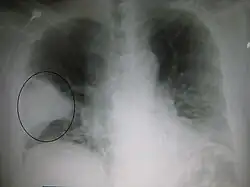

Większość bakterii dostaje się do płuc w drodze aspiracji niewielkich organizmów znajdujących się w gardle lub w nosie[11]. U połowy ludzi dokonuje się to w czasie snu[18]. W gardle zawsze znajdują się bakterie, jednak te mogące wywoływać infekcje występują tam tylko w określonym czasie i w określonych warunkach[18]. Niektóre typy bakterii, jak prątek gruźlicy (Mycobacterium tuberculosis) i Legionella pneumophila, dostają się do płuc z zakażonymi kropelkami unoszącymi się w powietrzu[11]. Bakterie mogą również być przenoszone drogą krwiopochodną[12]. Po przedostaniu się do płuc mogą one atakować przestrzenie pomiędzy komórkami i pęcherzykami, gdzie makrofagi i neutrofile próbują zneutralizować bakterie[32]. Neutrofile uwalniają również cytokiny, wywołując ogólną aktywację układu odpornościowego[33]. Powoduje to gorączkę, dreszcze i często występujące w bakteryjnym zapaleniu płuc zmęczenie[33]. Neutrofile, bakterie i płyn z sąsiednich naczyń krwionośnych wypełniają pęcherzyki płucne, powodując zagęszczenie widoczne na zdjęciu rentgenowskim klatki piersiowej[34].

W diagnozie często wykorzystuje się zdjęcie rentgenowskie klatki piersiowej[10]. W łagodnych postaciach choroby obrazowanie konieczne jest tylko w razie potencjalnych powikłań, niejasnej przyczyny choroby oraz u osób, których stan nie uległ poprawie mimo leczenia[10][37]. Prześwietlenie zalecane jest u osób w stanie na tyle poważnym, że wymagają hospitalizacji[37]. Wyniki jednak nie zawsze korelują ze stadium zaawansowania choroby i nie pozwalają na wiarygodne rozróżnienie pomiędzy infekcją o podłożu bakteryjnym a wirusowym[10].

Obrazy RTG zapalenia płuc można sklasyfikować jako przedstawiające płatowe zapalenie płuc, oskrzelowe zapalenie płuc (znane również jako zrazikowe zapalenie płuc) oraz śródmiąższowe zapalenie płuc[40]. Bakteryjne, pozaszpitalne zapalenie płuc w postaci klasycznej wykazuje konsolidację jednego segmentarnego płata płuca i znane jest jako płatowe zapalenie płuc[20]. Wyniki mogą jednak się różnić, a w innych typach zapalenia płuc powszechne są inne wzory zmian[20]. W aspiracyjnym zapaleniu płuc obraz może wykazywać dwustronną nieprzezroczystość głównie u podstawy płuc i po prawej stronie[20]. Obrazy wirusowego zapalenia płuc mogą wydawać się normalne, płuca nadmiernie rozdęte, z dwustronnymi niejednolitymi obszarami lub podobne do bakteryjnego zapalenia płuc z konsolidacją płata[20]. Zmiany mogą nie być widoczne w obrazach RTG we wczesnych stadiach choroby, zwłaszcza w wypadku odwodnienia; mogą być również trudne do zinterpretowania u osób otyłych lub z historią chorób płuc[11]. W ostatnich latach istotne badania kliniczne wykazały, że ultrasonografia klatki piersiowej, wykonywana przez doświadczonych specjalistów, charakteryzuje się dokładnością diagnostyczną równą, a nawet przewyższającą radiografię klatki piersiowej w diagnostyce zapalenia płuc. Podejście to znajduje coraz szersze zastosowanie w praktyce klinicznej[41]. W trudnych do określenia przypadkach dodatkowe informacje można uzyskać dzięki tomografii komputerowej[20].